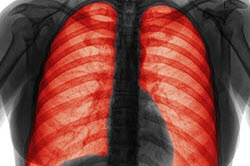

關于慢性阻塞性肺病的基礎知識

什么是慢性阻塞性肺病?

慢性阻塞性肺病或COPD是指一組導致氣流阻塞和呼吸相關問題的疾病。它包括肺氣腫和慢性支氣管炎。